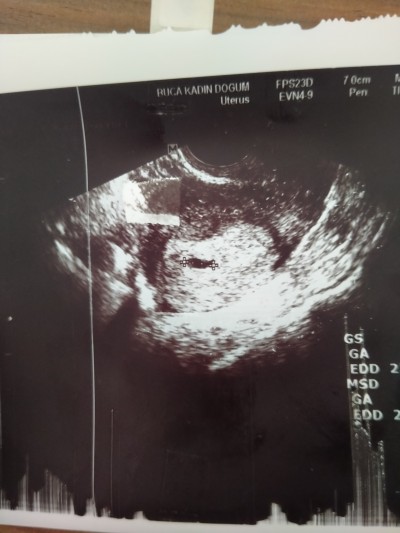

Bu gün doktora gittim vajinal ultrasonda kesemizi gördük kızlar 2 hafta sonra kalp atışı için gidicem inşallah kesemizde minicik daha ☺️

Gebelik haftası 5+1